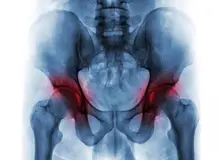

تعویض مفصل ران، که به عنوان تعویض کامل مفصل ران یا آرتروپلاستی کامل مفصل ران نیز شناخته میشود، یک عمل جراحی برای جایگزینی غضروف آسیبدیده در مفصل ران است. در این جراحی، بخشهای آسیبدیدهی مفصل توپی و حفرهای برداشته شده و با مواد مصنوعی فلزی، پلیاتیلن (پلاستیک) و/یا سرامیک جایگزین میشوند.